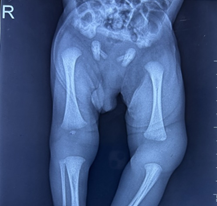

Considering the negative tests for sepsis and septic arthritis and persistence of, and slight increase in, knee swelling, plain radiographs of both knee joints were repeated on day 5 of life. The radiographs revealed swelling and a wide joint space in the left knee joint, along with valgus deformity of the femur. Surprisingly, the distal femoral epiphysis, visible by its ossified center, was seen to have lost alignment with the femur shaft but continued its alignment with the tibia (Figure 2), confirming the diagnosis of distal femoral epiphysiolysis.

Figure 2 Anteroposterior radiograph of both knee joints and lateral radiograph of left knee joint on day -5 of life showing a wide joint space in the left knee joint, along with valgus deformity of the femur. The distal femoral epiphysis, visible by its ossified center, has lost alignment with the femur shaft but continued its alignment with the tibia.